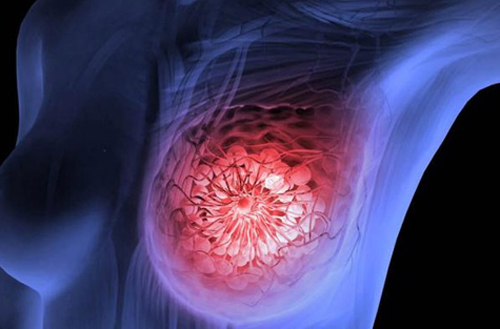

여성들이 많이 염려하는 암 중 하나가 바로 유방암인데요. 사실 유방암은 여성만 걸리는 병은 아니라 아주 드물게 남성도 걸린다고 합니다. 유방암은 매년 환자가 증가하는 추세인데, 2만 명 이상 환자가 늘어나고 있다고 해요. 특히 젊은층의 발병 사례가 늘어나고 있으므로 젊다고 안심해서는 안 될 것 같아요.

<유방암 초기증상>